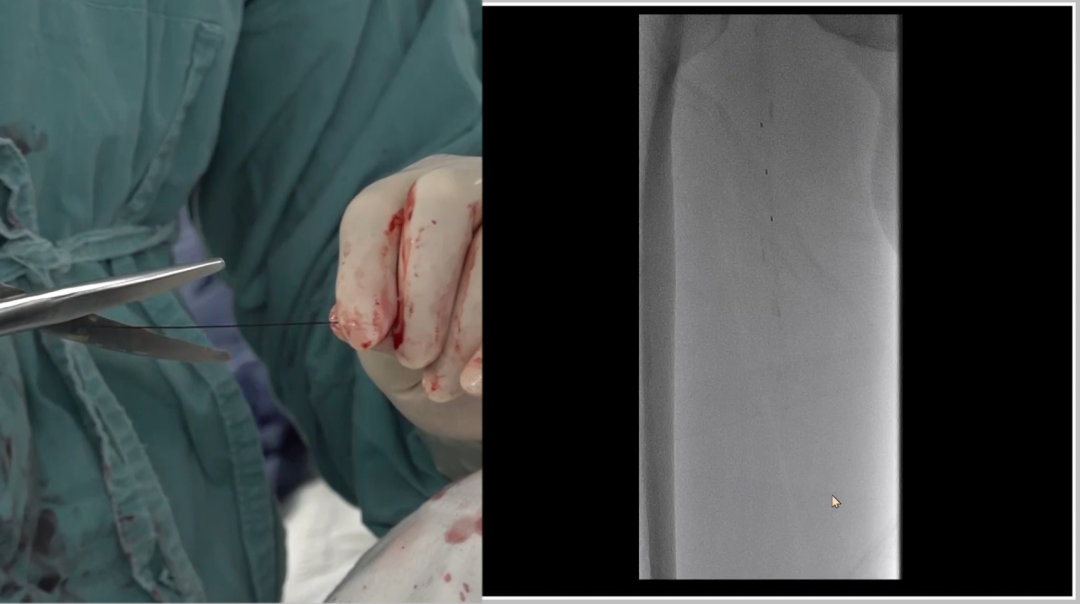

入路选择:左侧股动脉翻山入路

采用常规左侧股动脉穿刺,通过"翻山"技术到达右侧病变区域,为后续操作建立通路。

造影确认病变:长段闭塞,流出道尚可

造影显示右侧股动脉自起始段起长段闭塞,远端腘动脉及膝下动脉经股深侧枝显影,流出道条件尚可,为手术提供了基础。